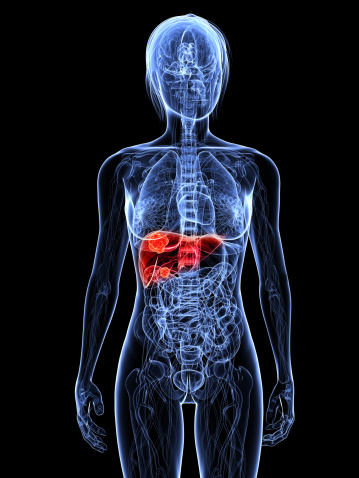

Top Sicknesses in the Emergency Room

On any given year, there are approximately 136 million visits to the emergency room and 41 percent of the population will seek out emergency room treatment. Although the ER often conjures up images of dramatic life or death situations such as bullet wounds or other bodily injuries, the majority of ER visits are not caused ...click here to read more